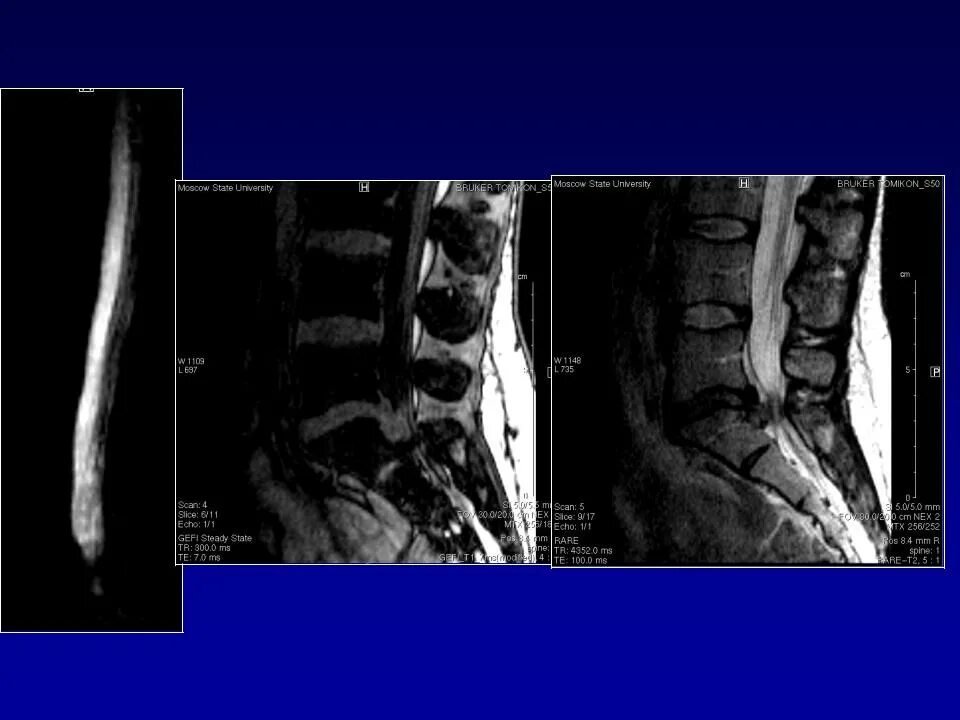

Грыжи дисков код по мкб